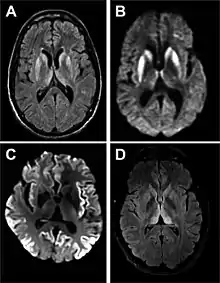

Magnetic resonance image of sporadic CJD[2]

Through the image of MRI, the obvious precipitation of prion protein in the brain is visible.

• MRI of the brain – often shows high signal intensity in the caudate nucleus and putamen bilaterally on T2-weighted images.

Imaging of the brain may be performed during medical evaluation, both to rule out other causes and to obtain supportive evidence for diagnosis. Imaging findings are variable in their appearance, and also variable in sensitivity and specificity.[43] While imaging plays a lesser role in diagnosis of CJD,[44] characteristic findings on brain MRI in some cases may precede onset of clinical manifestations.[45]

Brain MRI is the most useful imaging modality for changes related to CJD. Of the MRI sequences, diffuse-weighted imaging sequences are most sensitive.[46] Characteristic findings are as follows:

• Focal or diffuse diffusion-restriction involving the cerebral cortex and/or basal ganglia. In about 24% of cases DWI shows only cortical hyperintensity; in 68%, cortical and subcortical abnormalities; and in 5%, only subcortical anomalies.[47] The most iconic and striking cortical abnormality has been called "cortical ribboning" or "cortical ribbon sign" due to hyperintensities resembling ribbons appearing in the cortex on MRI.[48] The involvement of the thalamus can be found in sCJD, is even stronger and constant in vCJD.[49]

• Varying degree of symmetric T2 hyperintense signal changes in the basal ganglia (i.e., caudate and putamen), and to a lesser extent globus pallidus and occipital cortex.[44]